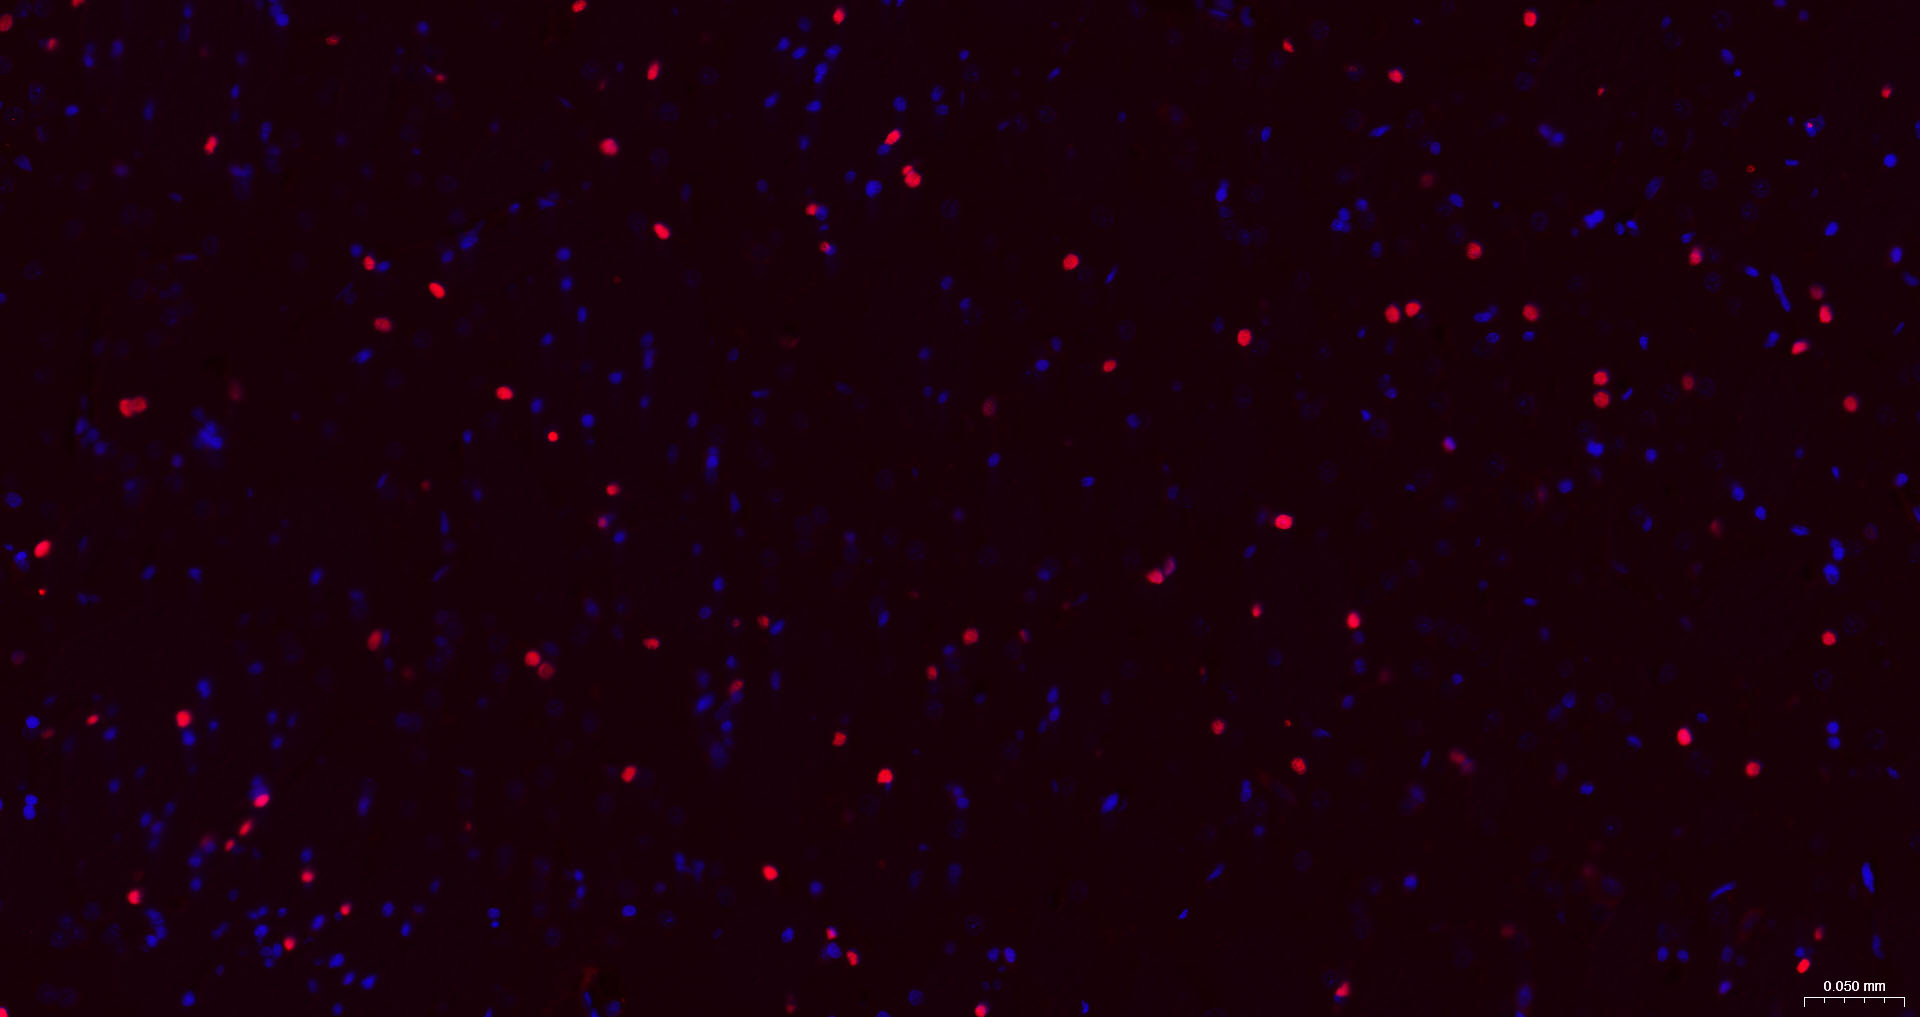

Paraformaldehyde-fixed, paraffin embedded Mouse Cerebrum; Antigen retrieval by boiling in sodium citrate buffer (pH6.0) for 15 min; The section was incubated with SOX9 Monoclonal Antibody, Unconjugated (bsm-63031R) at 1:200 overnight at 4°C. Followed by conjugated Goat Anti-Rabbit IgG antibody (Red, bs-0295G-BF594), DAPI (blue, C02-04002) was used to stain the cell nuclei.